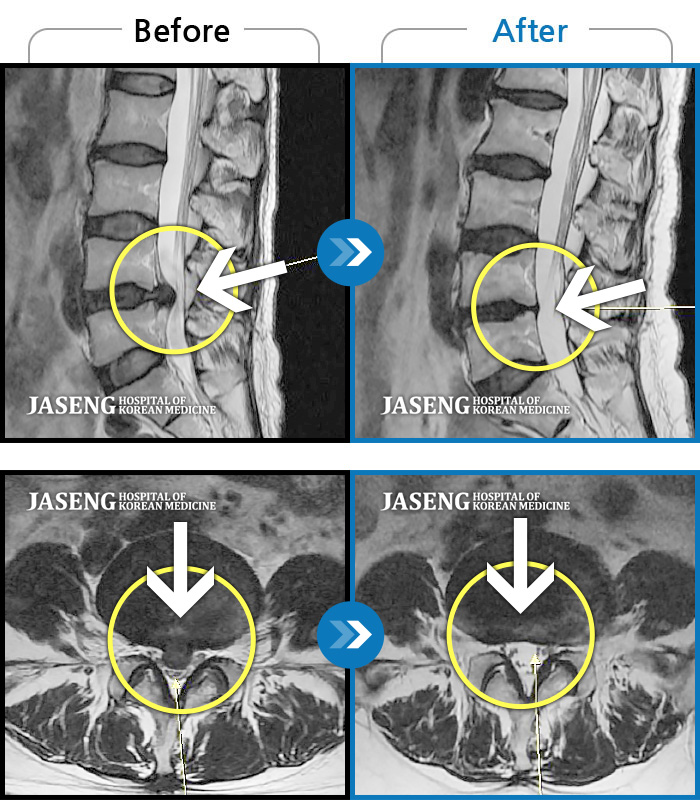

ȯںп Ǹ ǿ ԿǾ, ο ġ ۿ Ƿ ġḦ Ͻñ ٶϴ.